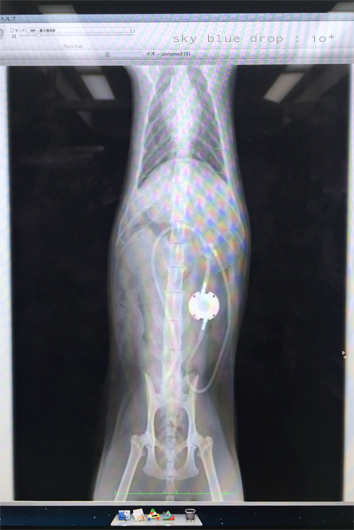

レントゲン画像ですがイオちゃんのお腹の中はこんな事になってます。

腎臓ー膀胱がチューブで繋がれています

丸っこく写っているのがポート部です。

ポート部は皮膚のすぐ下に設置されているので

もちろんこのままの状態で処置可能。

反対にココから尿を採取する事も出来るのだそう。

ご覧のとおり大きな人工物がお腹に入るので